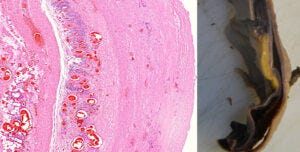

9. Endothelial stripping and destruction of a small blood vessel after vaccination

We now turn to the evidence of immune attack on the endothelial cells which produce the spike protein. On the left, a normal venule, delimited by an intact endothelium and containing some red blood cells and few white blood cells (stained blue) inside.

The image on at the centre shows a venule that is being attacked and destroyed by the immune system. The outline is already dissolving, and the spindle-shaped (and swollen) endothelial cells have peeled off from the vessel wall. Furthermore, we see lymphocytes—the small cells with dark, round nuclei and with very little cytoplasm around them; a single lymphocyte (at much higher magnification) is shown on the right.

Lymphocytes are the backbone of the specific immune system—whenever antigens are recognized and antibodies are produced, this is done by lymphocytes. Also among the lymphocytes we find cytotoxic T cells and natural killer cells, which serve to kill virus-infected cells—or ones that look to them as if infected, because they have been forced to produce a viral protein by a so-called vaccine.

A crucial function of the endothelium is to prevent blood clotting. Thus, if the endothelium is damaged, as it is in this picture, and the tissues beyond it make contact with the blood, this will automatically set off blood clotting.

10. A crack in the wall of the aorta, lined by clusters of lymphocytes, leading to aortic rupture

On the left, a section through the wall of an aorta. This picture is taken at an even lower magnification than the one before; the lymphocytes now appear as just a cloud of tiny blue specks. To the left of this blue cloud, we see a vertical crack running through the tissue. Such a crack is also visible macroscopically in the excised specimen of an aorta shown on the right.

The aorta is the largest blood vessel of the body. It receives the highly pressurized blood ejected by the left ventricle of the heart, and it is thus exposed to intense mechanical stress. If the wall of the aorta is weakened by inflammation, as it is here, then it may crack and rupture. Aortic rupture is normally quite rare, but Prof. Burkhardt found multiple cases in his limited number of autopsies. Some of the affected aortas were also shown to have expressed the spike protein.